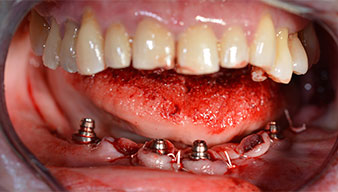

Dopo aver rimosso la dentatura residua dalla mandibola, la cresta alveolare viene esposta da 37 a 47.

Prima di tutto, è stato individuato il forame mentoniero come limite della struttura anatomica. Successivamente, l'osso corticale della cresta è stato lisciato con un manipolo e una fresa larga a rosetta (Fig. 4).